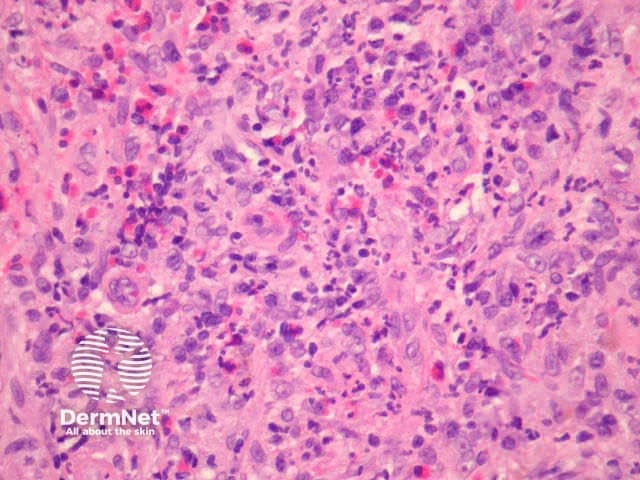

In erythema elevatum diutinum, there is sparing of the papillary and periadnexal dermis (Figures 1, 2). Vascular infiltration in the upper and mid-dermis with predominant neutrophils and fewer lymphocytes, eosinophils and plasma cells (Figures 3, 4, 5). Leucocytoclasia is commonly seen in fresh lesions (Figure 5). Later lesions develop sclerosis with plasma cells and residual foci of leukocytoclastic vasculitis. Sclerosis may be striking and have a storiform pattern (Figures 1, 4).

Figure 5